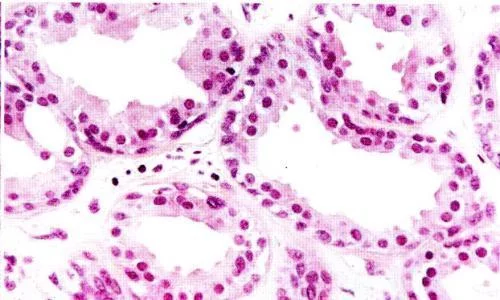

组织学上呈简单的单管状腺,有两层上皮细胞,即内层分泌细胞和外层肌上皮细胞。分泌物潴留,管腔扩张成腺泡或形成筛状。肿省过孙题会瘤表面被覆外耳道皮肤,肿瘤无包膜。